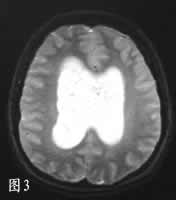

CT示双侧脑室肿物,呈泡沫状,实性部分有增强,双侧脑室轻度积水(图1)。MRI上肿瘤实性部分T1WI与T2WI均与白质信号相近,中度增强(图2、3),多囊内呈水样信号。